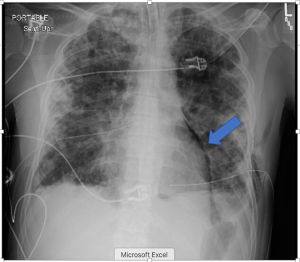

A 32-year-old male with a history of IV drug and tobacco use presented to the Emergency department with blunt chest trauma. He had pre-existing pulmonary septic emboli and developed severe acute respiratory distress syndrome (ARDS) requiring intubation and veno-venous extracorporeal membrane oxygenation (ECMO). While on ECMO he developed bilateral pneumothoraces from ruptured blebs complicated by bilateral bronchopleural fistulae. CT scan was obtained that revealed small volume pneumopericardium as well as bilateral pneumothoraces (Figure 1). Corresponding chest X-ray is seen in Figure 2. Several days after ECMO decannulation the patient developed acute agitation and hemodynamic instability. A chest X-ray was obtained that revealed air in the pericardial sac, cardiac compression, and mediastinal shift consistent with tension pneumopericardium (Figure 3). He was taken emergently to the operating room for pericardial window and drain placement. He was returned to the surgical ICU in critical, but improved, condition. Though rare, tension pneumopericardium should be on the differential diagnosis for shock in patients with blunt chest trauma, emphysematous lung disease, or bronchopleural fistula.